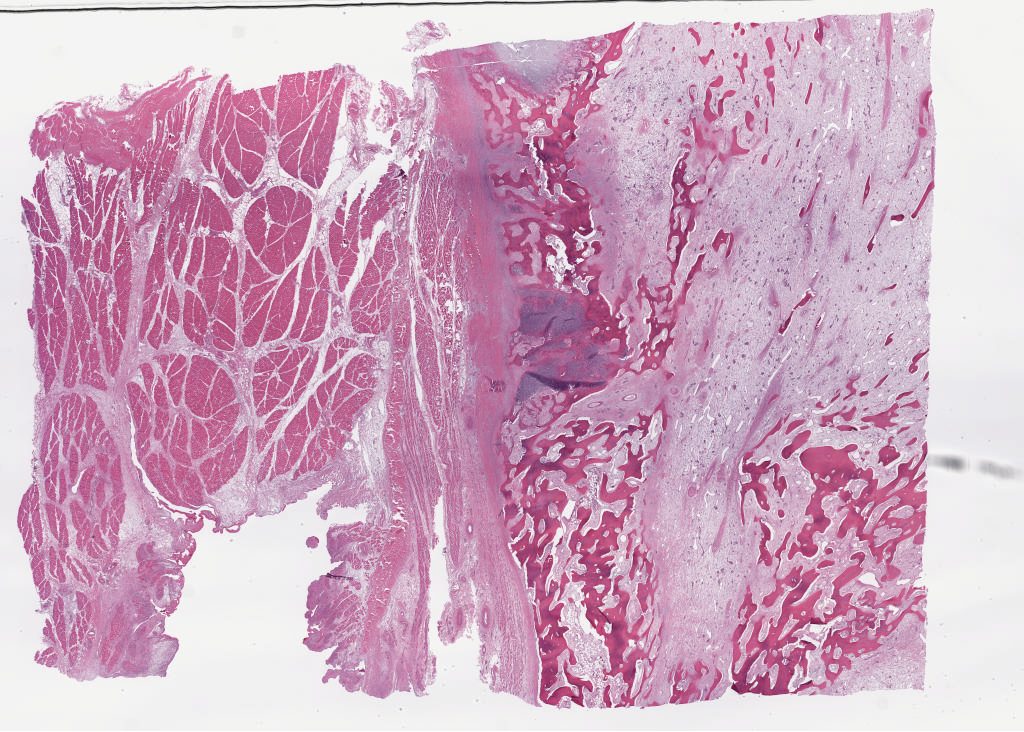

2059579.svs

2059673.svs